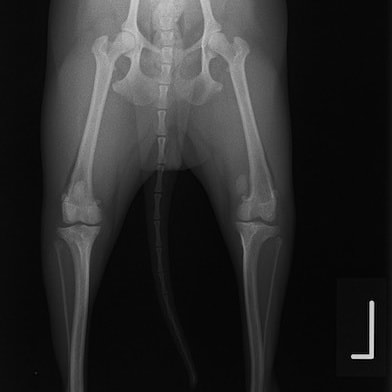

■ 症例24 キャバリア 7か月

左右膝蓋骨内方脱臼(左:グレードⅣ 右:グレードⅢ)

以前から左右後肢の跛行が認められ、整形外科学的検査・レントゲン検査により左右の膝蓋骨脱臼が認められた。症状が重度である左膝の膝蓋骨脱臼整復術を行った。外科手技は縫工筋及び内側広筋の解放、脛骨粗面の外側転位、滑車ブロック形造溝術、内外側関節方の縫縮を実施した。術後一か月時点で、左の膝蓋骨は安定しており経過は良好である。

本症例は成長期における重度の膝蓋骨脱臼であり、術後の再発の可能性もあるため、経過をしっかりと観察していく必要がある。また、今回手術を実施していない右膝に関しても経過を観察し、手術を検討していくこととする。